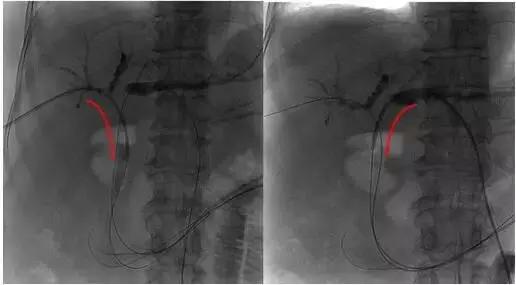

2、插入射频消融导管